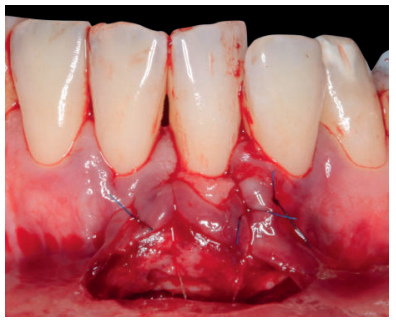

Previamente a la intervención, la paciente se enjuagó durante 1 minuto con un colutorio de clorhexidina. La técnica quirúrgica comenzó con la preparación del lecho receptor, para ello se realizó una incisión sulcular a espesor parcial a nivel de la recesión, se continúo diseccionando apical y lateralmente, extendiéndose de 3 a 5 mm de la recesión para permitir la entrada del ITC y su estabilización. Posteriormente, se realizó una incisión en el fondo de vestíbulo, dejando un puente de tejido que servirá para un doble aporte sanguíneo al injerto (Figura 2).

Una vez creado el lecho receptor, se procedió a la obtención de un ITC de la mucosa masticatoria palatina y a la sutura de dicho injerto mediante dos puntos colchoneros horizontales, uno situado en la parte mesial y otro en la parte distal del sobre. Para mayor adaptación y estabilización de las papilas se realizó un punto suspensorio cogiendo papila e ITC, mediante sutura de 6/0 no reabsorbible (Figura 3).